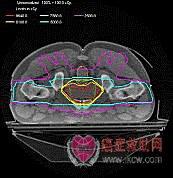

7)3D适形调强放射治疗设备(3D Conformal and Intensity Modulation-IMRT)

与3D适形放射治疗设备的区别是:3D Conformal仅仅是几何形状的符合,辐射野内的剂量强度是均匀的。而IMRT 则要求不仅几何形状符合,辐射野内的剂量强度也要根据临床要求实时调变。从一定意义上讲,IMRT几乎完美地满足了避免照射和提高肿瘤局部控制率的新要求。

8)图象引导放射治疗设备(Image Guide RadioTherapy-IGRT)

当今进入临床推广应用的最先进的医用电子直线加速器放疗设备。